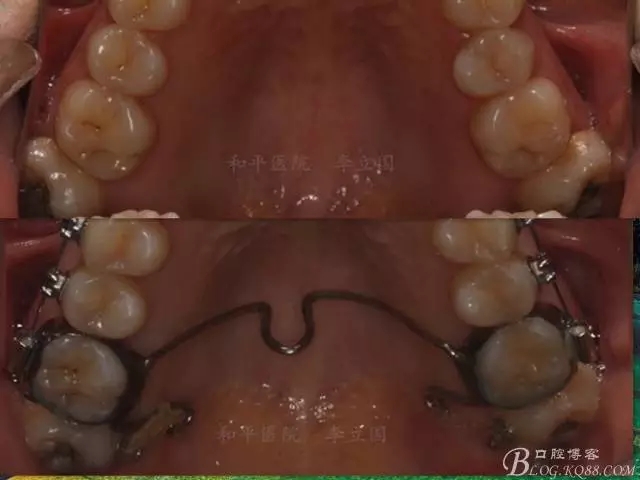

該病例主要為17、27頰側(cè)位同時伴有伸長,當然種植支抗可以解決,但還有簡單實用的辦法嗎?如圖,在橫腭桿遠中延伸出牽引鉤,位置盡量遠離合平面,7粘舌側(cè)扣,牽引力的方向為壓低及舌向,下圖為兩個月的效果,17已到位,27還未到位。